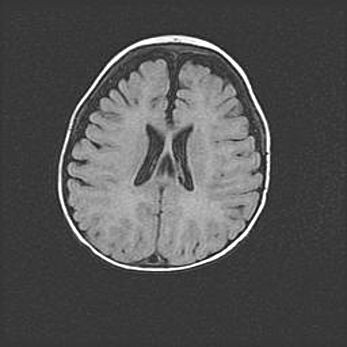

Наружная гидроцефалия с возможной атрофией височных областей.

Возраст: 28 дней

Вес: 3670 г

Пол: мужской

Окружность головы: 38 см

Срок гестации: 40 недель

Гидроцефалия головного мозга у новорожденных – это заболевание, которое характеризуется скоплением избыточного количества спинномозговой жидкости в желудочковой системе головного мозга в результате затруднения её перемещения от места выработки к месту поглощения в кровеносную систему или вследствие нарушения абсорбции. При открытой наружной форме гидроцефалии у новорожденных расширяются и переполняются субарахноидные пространства.

При нормотензивных  формах,  которые,  как  правило,  являются  следствием  перенесенных ишемических  повреждений  паренхимы  мозга,  возможно  сочетание микроцефалии  с нормотензивной гидроцефалией. В основе данных изменений лежит атрофия больших полушарий с преимущественной  локализацией  в  лобно-височных  областях.